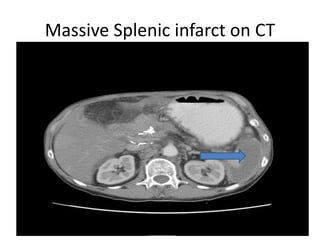

• CT scan and Radionuclide scan: Typically seen

as localized wedge shaped defects in splenic

parenchyma.

In the chronic phase, infarcts may disappear

completely, but more commonly, they may

reveal progressive volume loss caused by fibrotic

contraction of the infarct.

Massive Splenic infarct on CT